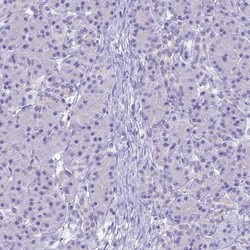

- Immunohistochemistry-Paraffin: UNC80 Antibody [NBP1-94110] - Staining of human cerebral cortex shows high expression.

- Immunohistochemistry-Paraffin: UNC80 Antibody [NBP1-94110] - Staining of human pancreas shows low expression as expected.

- Immunohistochemistry-Paraffin: UNC80 Antibody [NBP1-94110] - Staining in human cerebral cortex and pancreas tissues using anti-UNC80 antibody. Corresponding UNC80 RNA-seq data are presented for the same tissues.